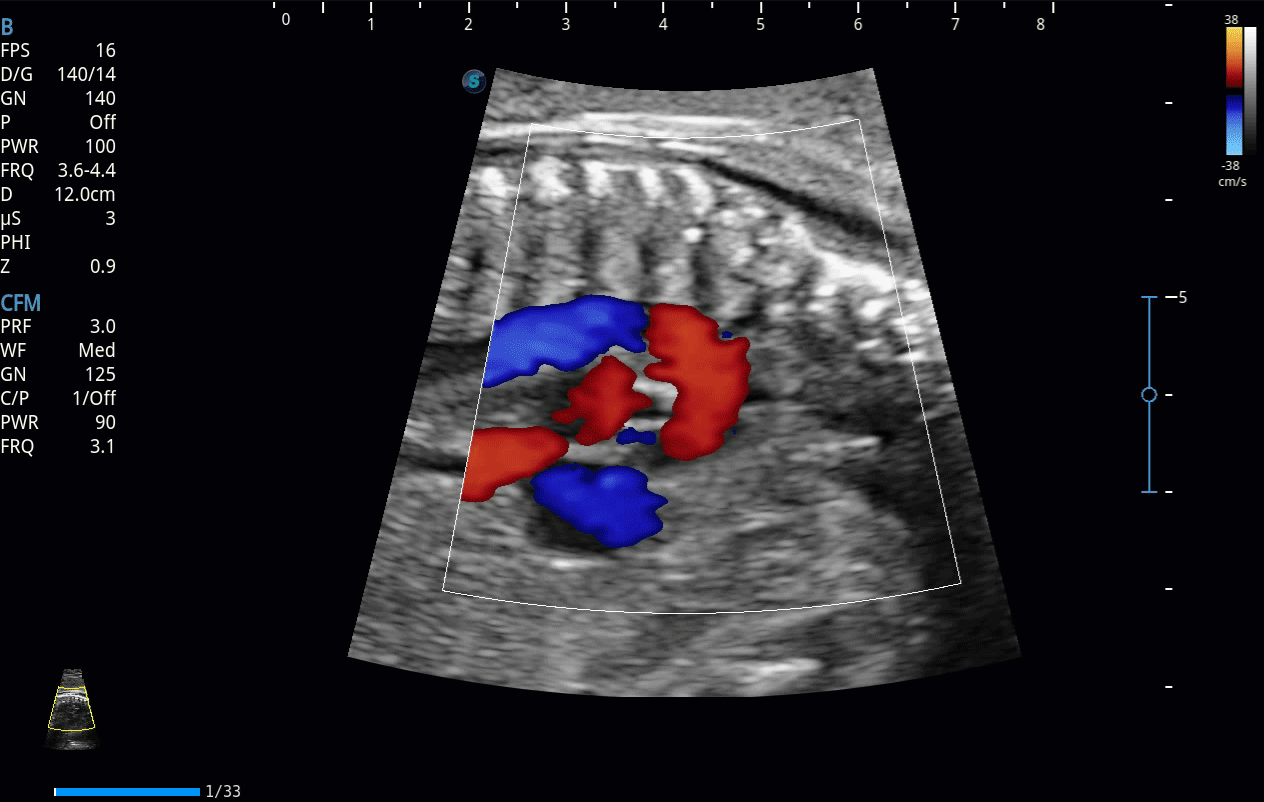

彩色多普勒超聲診斷系統(tǒng)

開(kāi)立醫(yī)療通過(guò)不斷的技術(shù)創(chuàng)新,為大眾的生命健康提供持續(xù)關(guān)愛(ài)。P12 Plus采用全新一代超聲成像平臺(tái),新平臺(tái)旨在將真實(shí)還原組織解剖結(jié)構(gòu)作為首要目標(biāo)。平臺(tái)采用全新集成化硬件模塊,搭載新一代芯片,系統(tǒng)性能得到大幅提升,為您的診斷提供了豐富的臨床信息。優(yōu)異的圖像表現(xiàn),豐富的探頭配置,全面的應(yīng)用功能,為您日常診斷提供了可靠的助手。